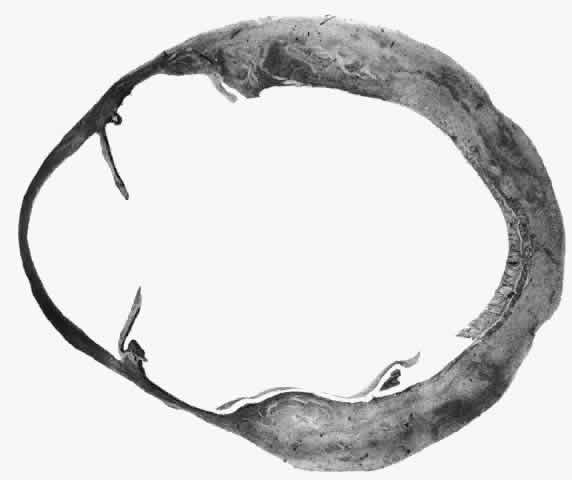

of the eye. A posterior scleritis often occurs as an extension of anterior

disease; but, as in Figure 20, most of the inflammation (in some cases all of the inflammation) is in

the posterior segment and the exudative detachments and subretinal granulomas

Fig. 20. Posterior scleritis. This eye was removed because of loss of vision and

pain, mistakenly diagnosed as malignant melanoma. (Courtesy of Professor N. Ashton) Fig. 20. Posterior scleritis. This eye was removed because of loss of vision and

pain, mistakenly diagnosed as malignant melanoma. (Courtesy of Professor N. Ashton)